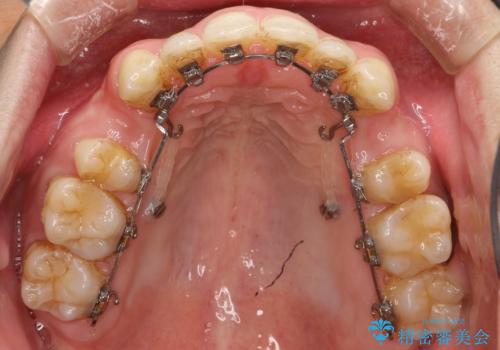

前歯の隙間を閉じたい 口元も下げたい ハーフリンガルによる抜歯矯正

- 矯正装置

- ハーフリンガル

上顎正中離開と、口唇の突出感がありました。

上下左右の歯を1本ずつ抜歯しして、上顎の前歯を後方に移動させるのと、正中の隙間を閉じる計画としました。

装置はなるべく目立たないものをご希望でしたので、ハーフリンガルを選択されました。